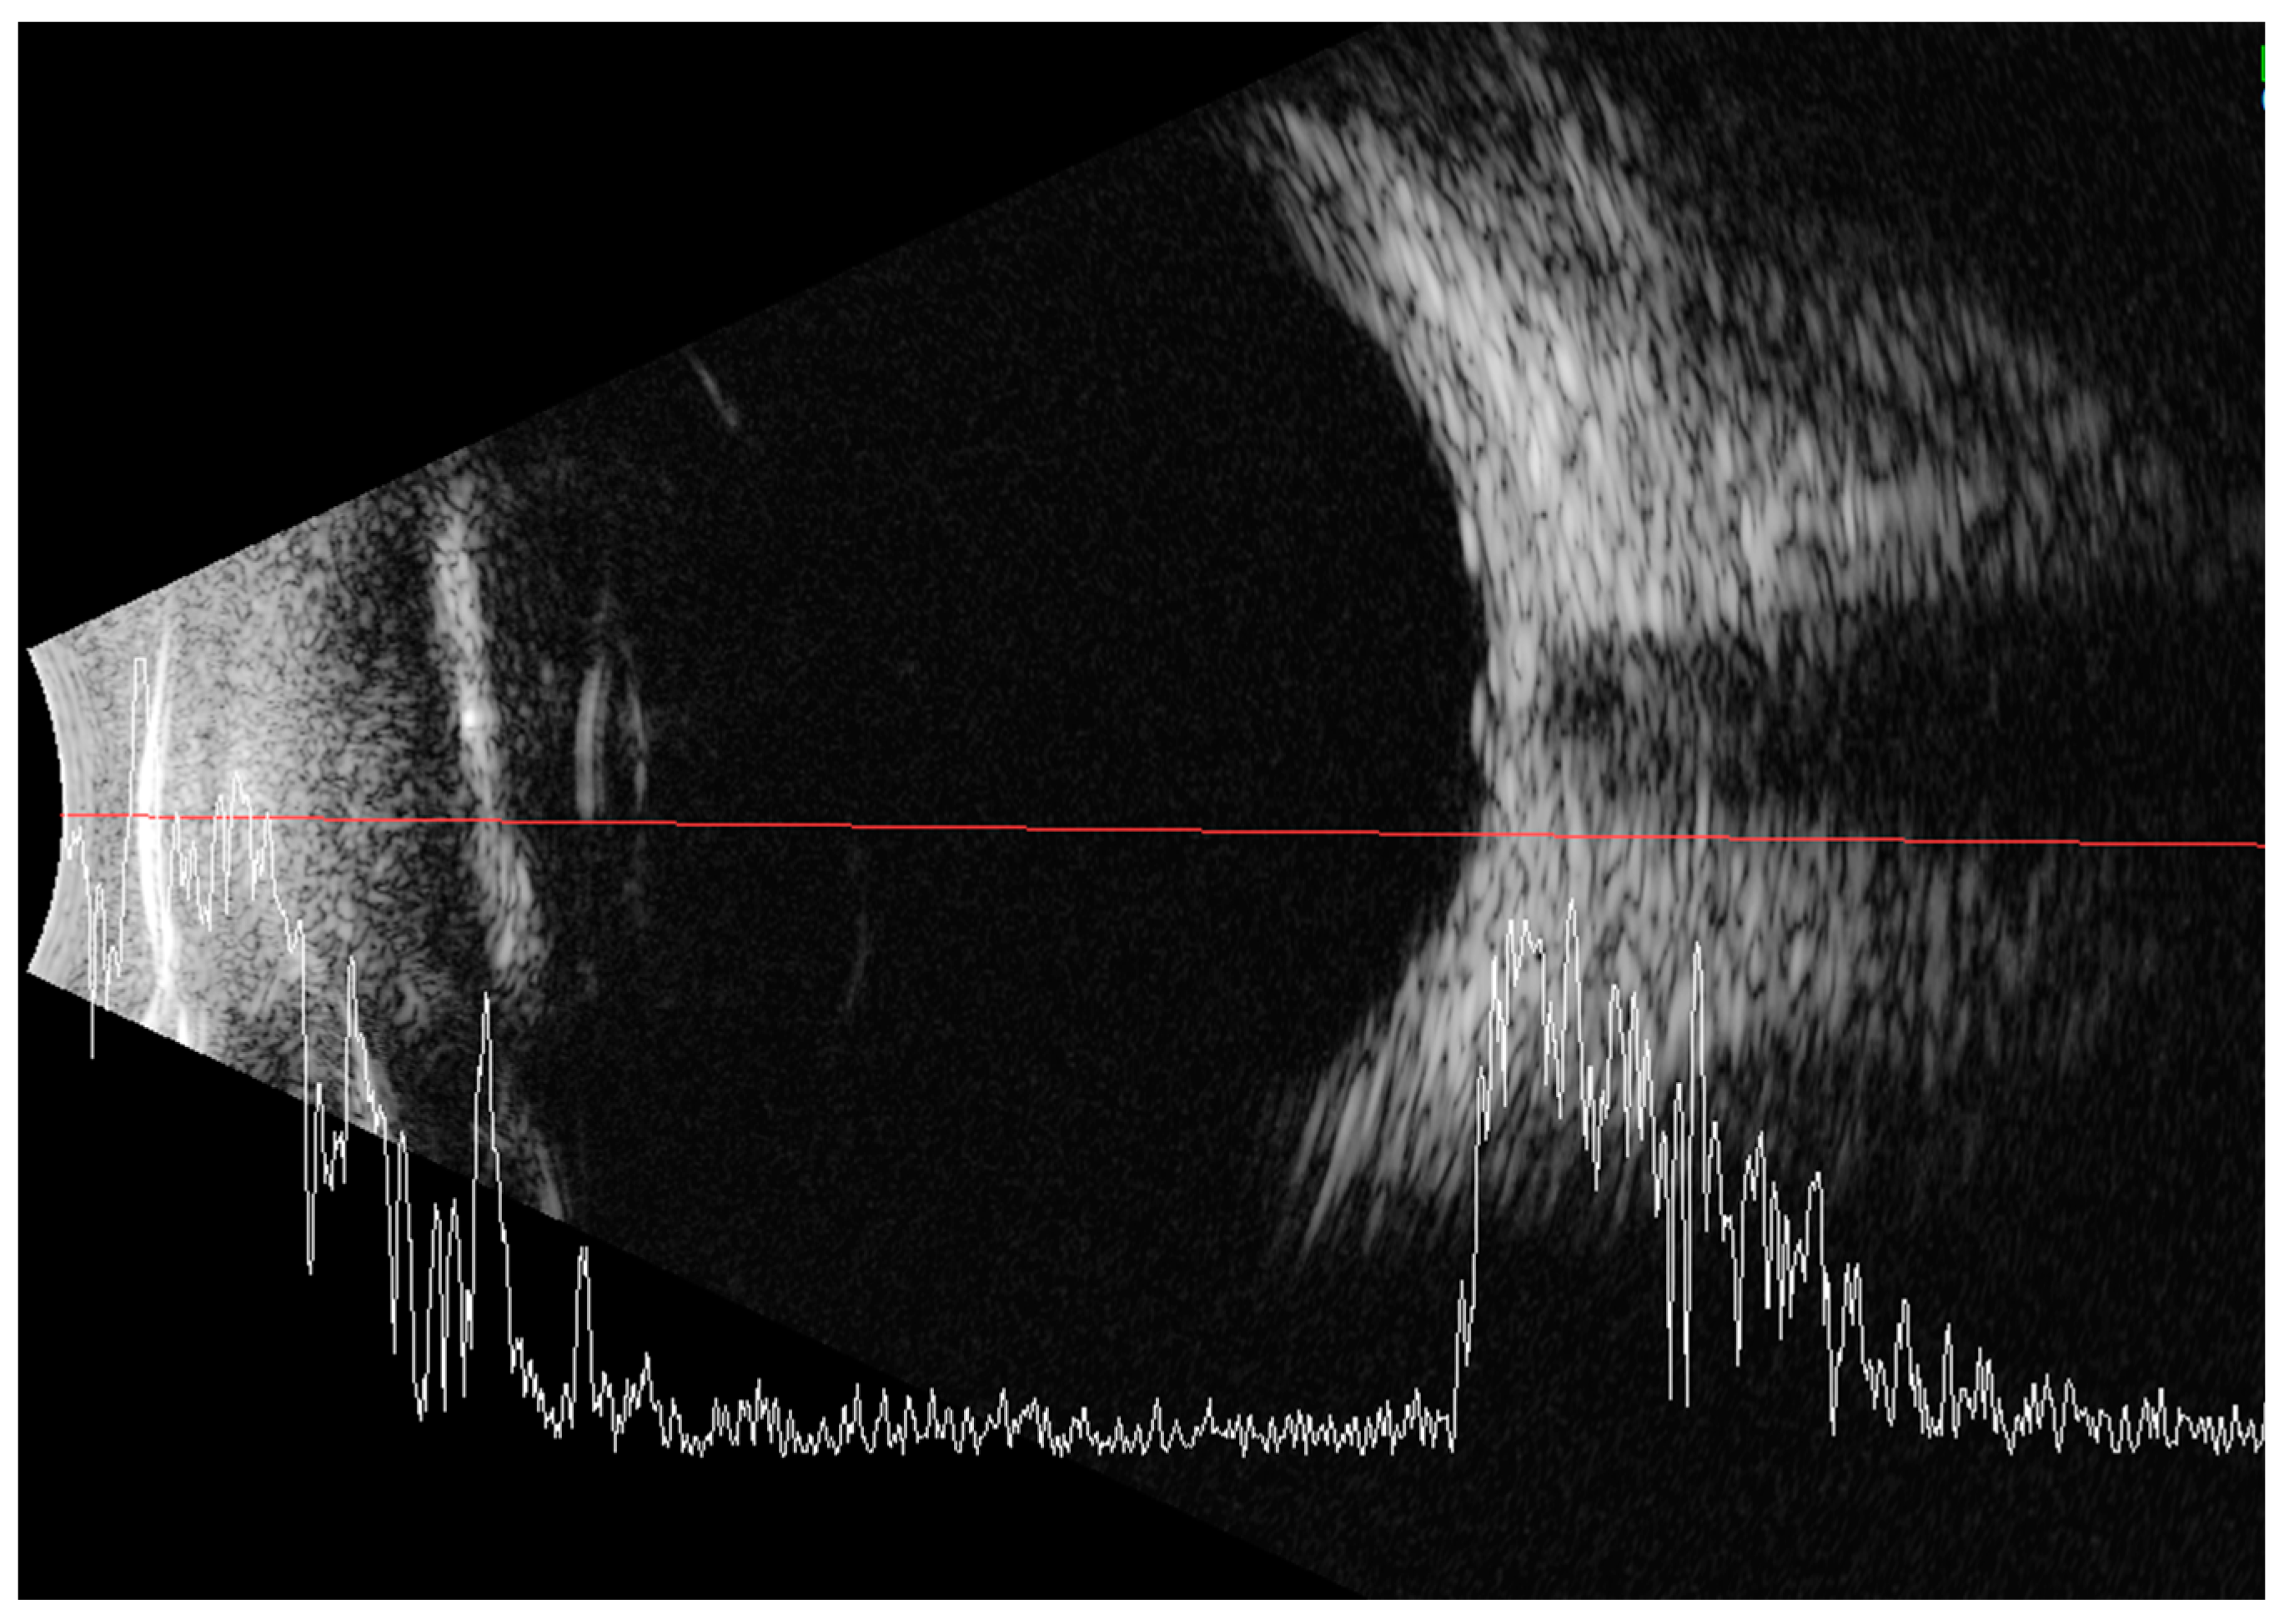

2. Case Report